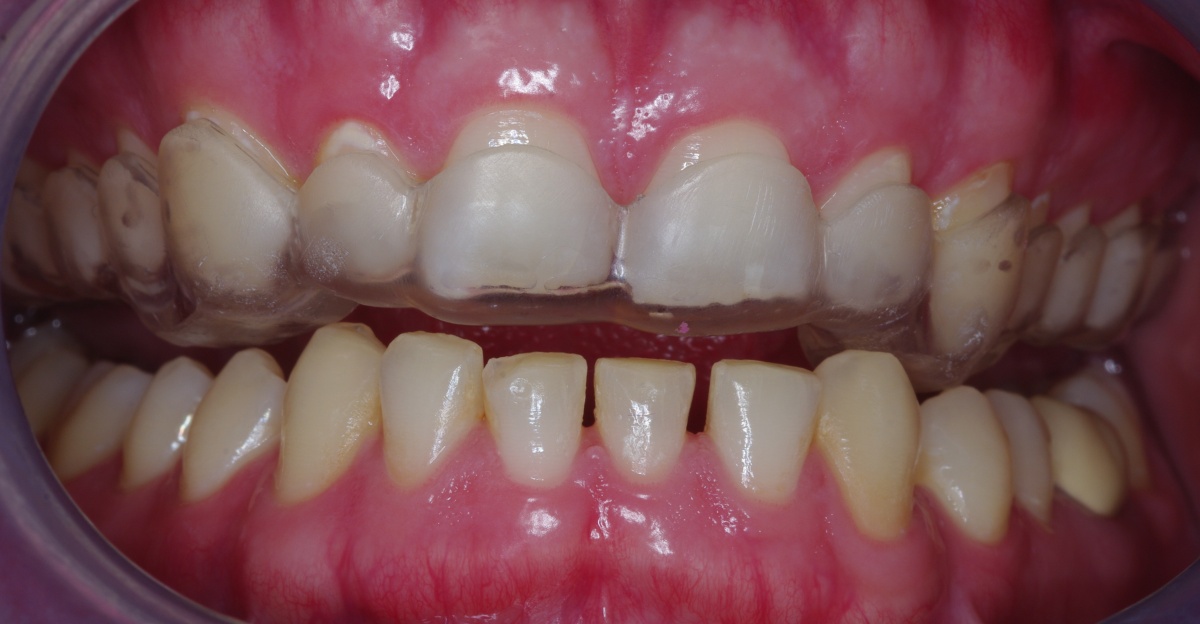

Zahnhartsubstanzdefekte von mehr als 50 % der Kronenlänge verursachen häufig kostenintensive prothetische Folgekosten bei geringer Haltbarkeit dieser Versorgungen (Wetselaar et al. 2009). Sichtbarer Verlust an Zahnhartsubstanz, ohne Kariesursache („Toothwear“) als Attrition durch Bruxismus verursacht, kann durch Erosion von Säure (Nahrung, Erbrechen) und Abrasion (meist auf die Anwendung von groben Zahnpasten und aggressiven Zahnputztechniken zurückzuführen) verstärkt werden. Zur Quantifizierung der verlorenen Zahnhartsubstanz erfolgte die Bestimmung des Tooth Wear Index an Ober- und Unterkiefermodellen (mod. TWI 0 – 7 n. Wetselaar et al. 2009).

CMD und Bruxismus sind unterschiedliche Krankheitsbilder. Der Vorhersagewert von vorhandenen Attritionen durch Zahnknirschen für eine PTBS-Entwicklung wurde in einem retrospektiven wehrmedizinischen Sonderforschungsprojekt (12K1-S-80 1414) durch unsere Arbeitsgruppe eruiert. Die vorgelegte Untersuchung belegt, dass an PTBS erkrankte Soldaten aus Kriegseinsätzen signifikant häufiger schmerzhafte orofaziale Funktionsstörungen (bei 80 % konnte ein Kiefergelenksknacken beobachtet werden, 100 % litten unter schmerzhaften Muskelbefunden) entwickeln. Hierbei ergaben sich hohe Korrelationen für chronische Schmerzwerte der Kiefer- und Gesichtsmuskulatur (GCS-Fragebogen, DentaConcept), eingeschränkter Mundöffnung (31,4 ± 8,0 mm), Stressparametern (DASS-Fragebogen, DentaConcept) und ausgeprägten Zahnattritionen (> 30 % der natürlichen Zahnkronenlänge) mit der PTBS-Entwicklung im Vergleich zu einer Kontrollgruppe die über vergleichbare Auslandseinsatzbelastung, Alter, Geschlecht und Zahnzahl verfügte. 80 % der PTBS-Patienten hatten vor der stationären Aufnahme neben einer Blut- und Verletzungsphobie ebenfalls eine Zahnbehandlungsphobie entwickelt und über mehr als zwei Jahre keinen Zahnarzt für Behandlungs- oder Präventionsmaßnahmen aufgesucht.

Eingliederung einer Kunststoff-Relaxationsschiene (Interceptor) im Oberkiefer mit gleichzeitigen Kontakten regio 13/14 sowie 23/24 zur Eckzahnführung bei Protrusion und Laterotrusion. (Abb. 1)

Eingliederung einer adjustierten Dauerschiene mit Front-Eckzahnführung (zum Beispiel Michiganschiene) und Bisshebung nach erneuter Gesichtsbogenübertragung oder individuelle Schienengestaltung bei fehlenden Seitenzähnen (Abb. 2).

Falls notwendig Bisshebung nach Waxup (Abb. 3 und 4) vor folgender Kronen- und Brückenversorgung.